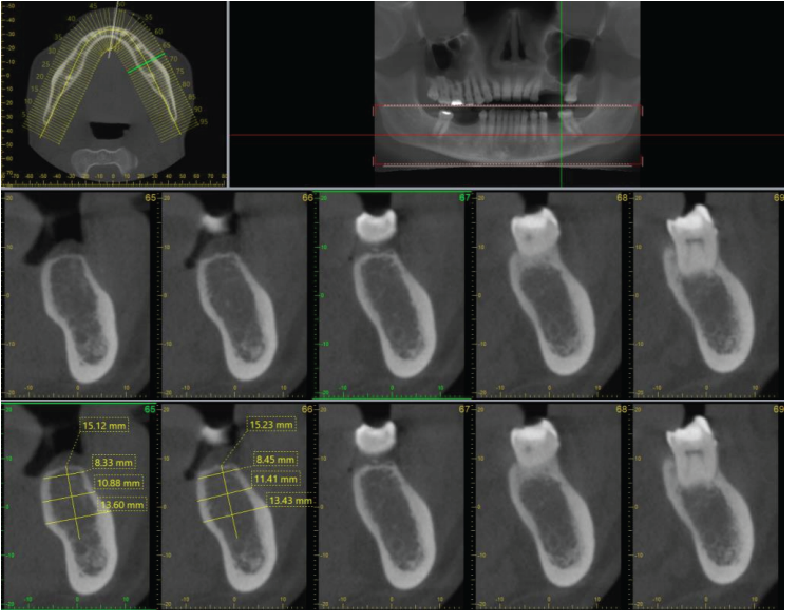

Image 3

Image 4

Periodontal bone levels are mainly normal or show mild bone loss, but there is greater bone loss associated with UR8 and UR7 and incidental finding of caries. UL4, UL5, UL6 sites have a mature alveolar ridge. No retained roots or bony pathosis. Selected images 3 are bucco-palatal cross-sections across the site. Bone height to the antral floor steadily falls moving distally across the site. There is a short transverse septum at the maxillary antral floor above the palatal side of UL5 site, which should not be relevant to any sinus lift procedure being planned. The alveolar bone quality appears satisfactory, with fairly dense trabeculation and well-defined cortices. The LL6 site has a mature alveolar ridge with no retained roots or bony pathothis. LL7 is mesially inclined, so that its crown overhangs the site. Selected images 4 are bucco-lingual cross-sections across the site. The alveolar ridge has a broad crest. There is a mild lingual undercut, with a lingual concavity present mesially in the site and in the premolar region. The lingual concavity of the submandibular fossa appears towards the distal end of the site. The ID canal is easily identified, lying quite low in the bone. The mental canal is in the plane of LL5. Bone quality is satisfactory, with well-defined thick cortices and fairly evenly trabeculated medullary bone.